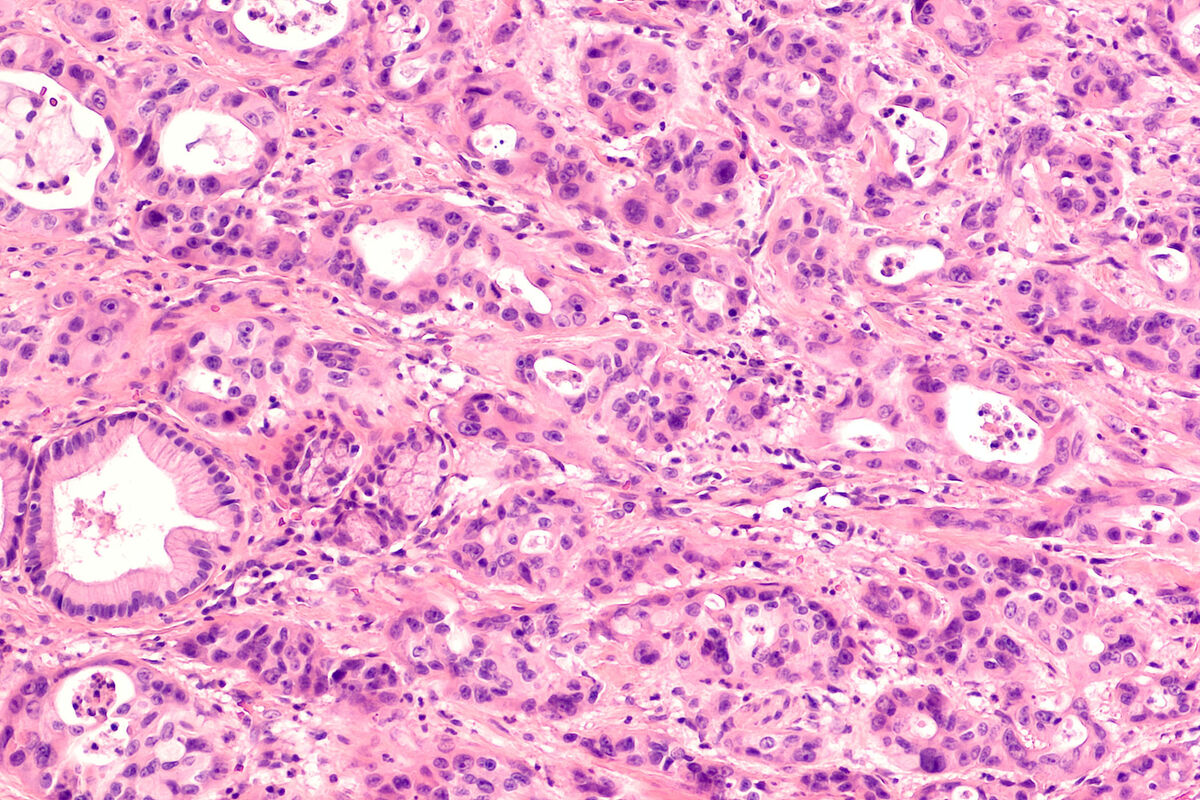

Однако некоторые опухоли в силу физиологических особенностей сложно контролировать даже на ранних стадиях. К ним относятся аденокарцинома поджелудочной железы, мелкоклеточный рак легкого, меланома и глиобластома головного мозга.

Как обратил внимание специалист, рак поджелудочной железы, несмотря на достаточно редкую встречаемость у пациентов, является одним из лидеров по смертности. Россия входит в число стран с высокой заболеваемостью наряду с Китаем, США и Германией. Сложность диагностики аденокарциномы (опухоль поджелудочной) — основная причина неблагоприятного прогноза. Опухоль долгое время развивается бессимптомно, а первые проявления (тошнота, тяжесть в животе, боли в левом подреберье) возникают лишь на поздних стадиях.

«Радикальная операция по удалению поджелудочной железы на ранней стадии обеспечивает пятилетнюю выживаемость лишь у 20% пациентов. На четвертой стадии этот показатель снижается до минимальных 1,5–3%», — отметил Макаров.